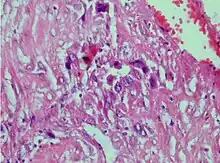

| Photomicrograph showing proliferating intermediate trophoblast with scarce cytotophoblastic and syncytiotrophoblastic elements | |

A placental site trophoblastic tumor is a monophasic neoplasm of the implantation site intermediate trophoblast, and usually a benign lesion, which comprises less than 2% of all gestational trophoblastic proliferations. Preceding conditions include molar pregnancy (5%). Compared to choriocarcinoma or invasive mole, hemorrhage is less conspicuous and serum β-HCG level is low, making early diagnosis difficult.

Immunohistochemistry often shows positive staining for hPL,[4][5] keratin,[5] Mel-CAM,[5] and EGFR.,[4] This immunohistochemical profile, particularly the strong positivity for hPL and Mel-CAM, along with the negative or focal staining for β-hCG and p63, helps distinguish PSTT from other types of gestational trophoblastic neoplasia such as choriocarcinoma and epithelioid trophoblastic tumour.[5]